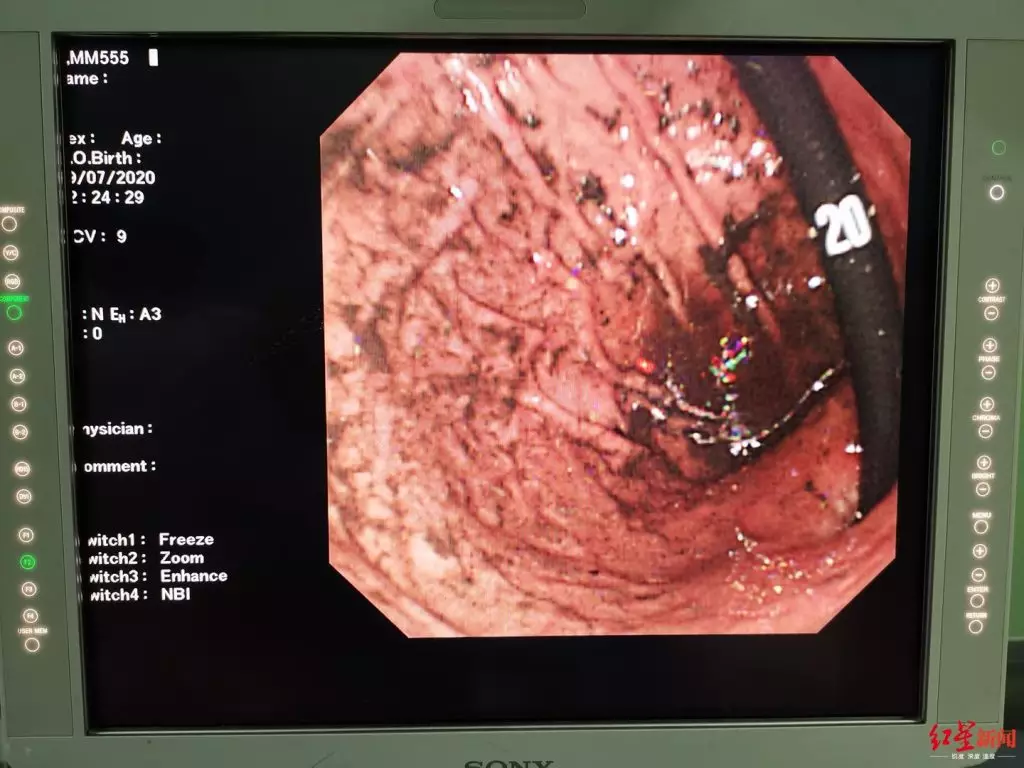

胃鏡下看到,點點胃裏全是纏繞的頭髮

點點來到四川大學華西醫院後,消化內科內鏡中心的鄧凱醫生為點點安排了「無痛胃鏡下異物取出術」,希望在明確胃內異物性質的同時儘可能通過內鏡取出異物。鄧凱醫生髮現,點點胃腸道里確實堆積了大量頭髮,胃腔明顯梗阻。因為頭髮太多,無痛胃鏡操作時所使用的靜脈麻醉的鎮靜效果較短較淺,無法一次性安全地取出所有異物,鄧凱醫生建議在手術室氣管插管全身麻醉狀態下再次嘗試異物取出。隨後鄧凱醫生立即聯繫了四川大學華西醫院小兒外科的楊敏醫生安排進一步治療。

「患兒的胃腔幾乎都被纏繞的頭髮佔滿了,只能一點一點地、一次一次地嘗試取。」楊敏醫生介紹說,“消化內科鄧凱醫生及其團隊,從當晚的10點一直堅持到次日的中午1點,整個手術過程持續了近15個小時;鄧凱醫生幾次都覺得可能沒辦法完全取出來,但想到孩子太小了,還是不甘心,還想再試試。”楊敏醫生說,我們小兒外科醫生全程陪同,也同時做好了後續準備,一旦確定微創手術無法全部取出,隨即採取開腹手術的方式取出異物;但手術創傷的確較大、恢復較慢、風險較大,何況患兒還是一個9歲的孩子。

手術後,胃裏的頭髮基本被清除乾淨 四川大學華西醫院供圖